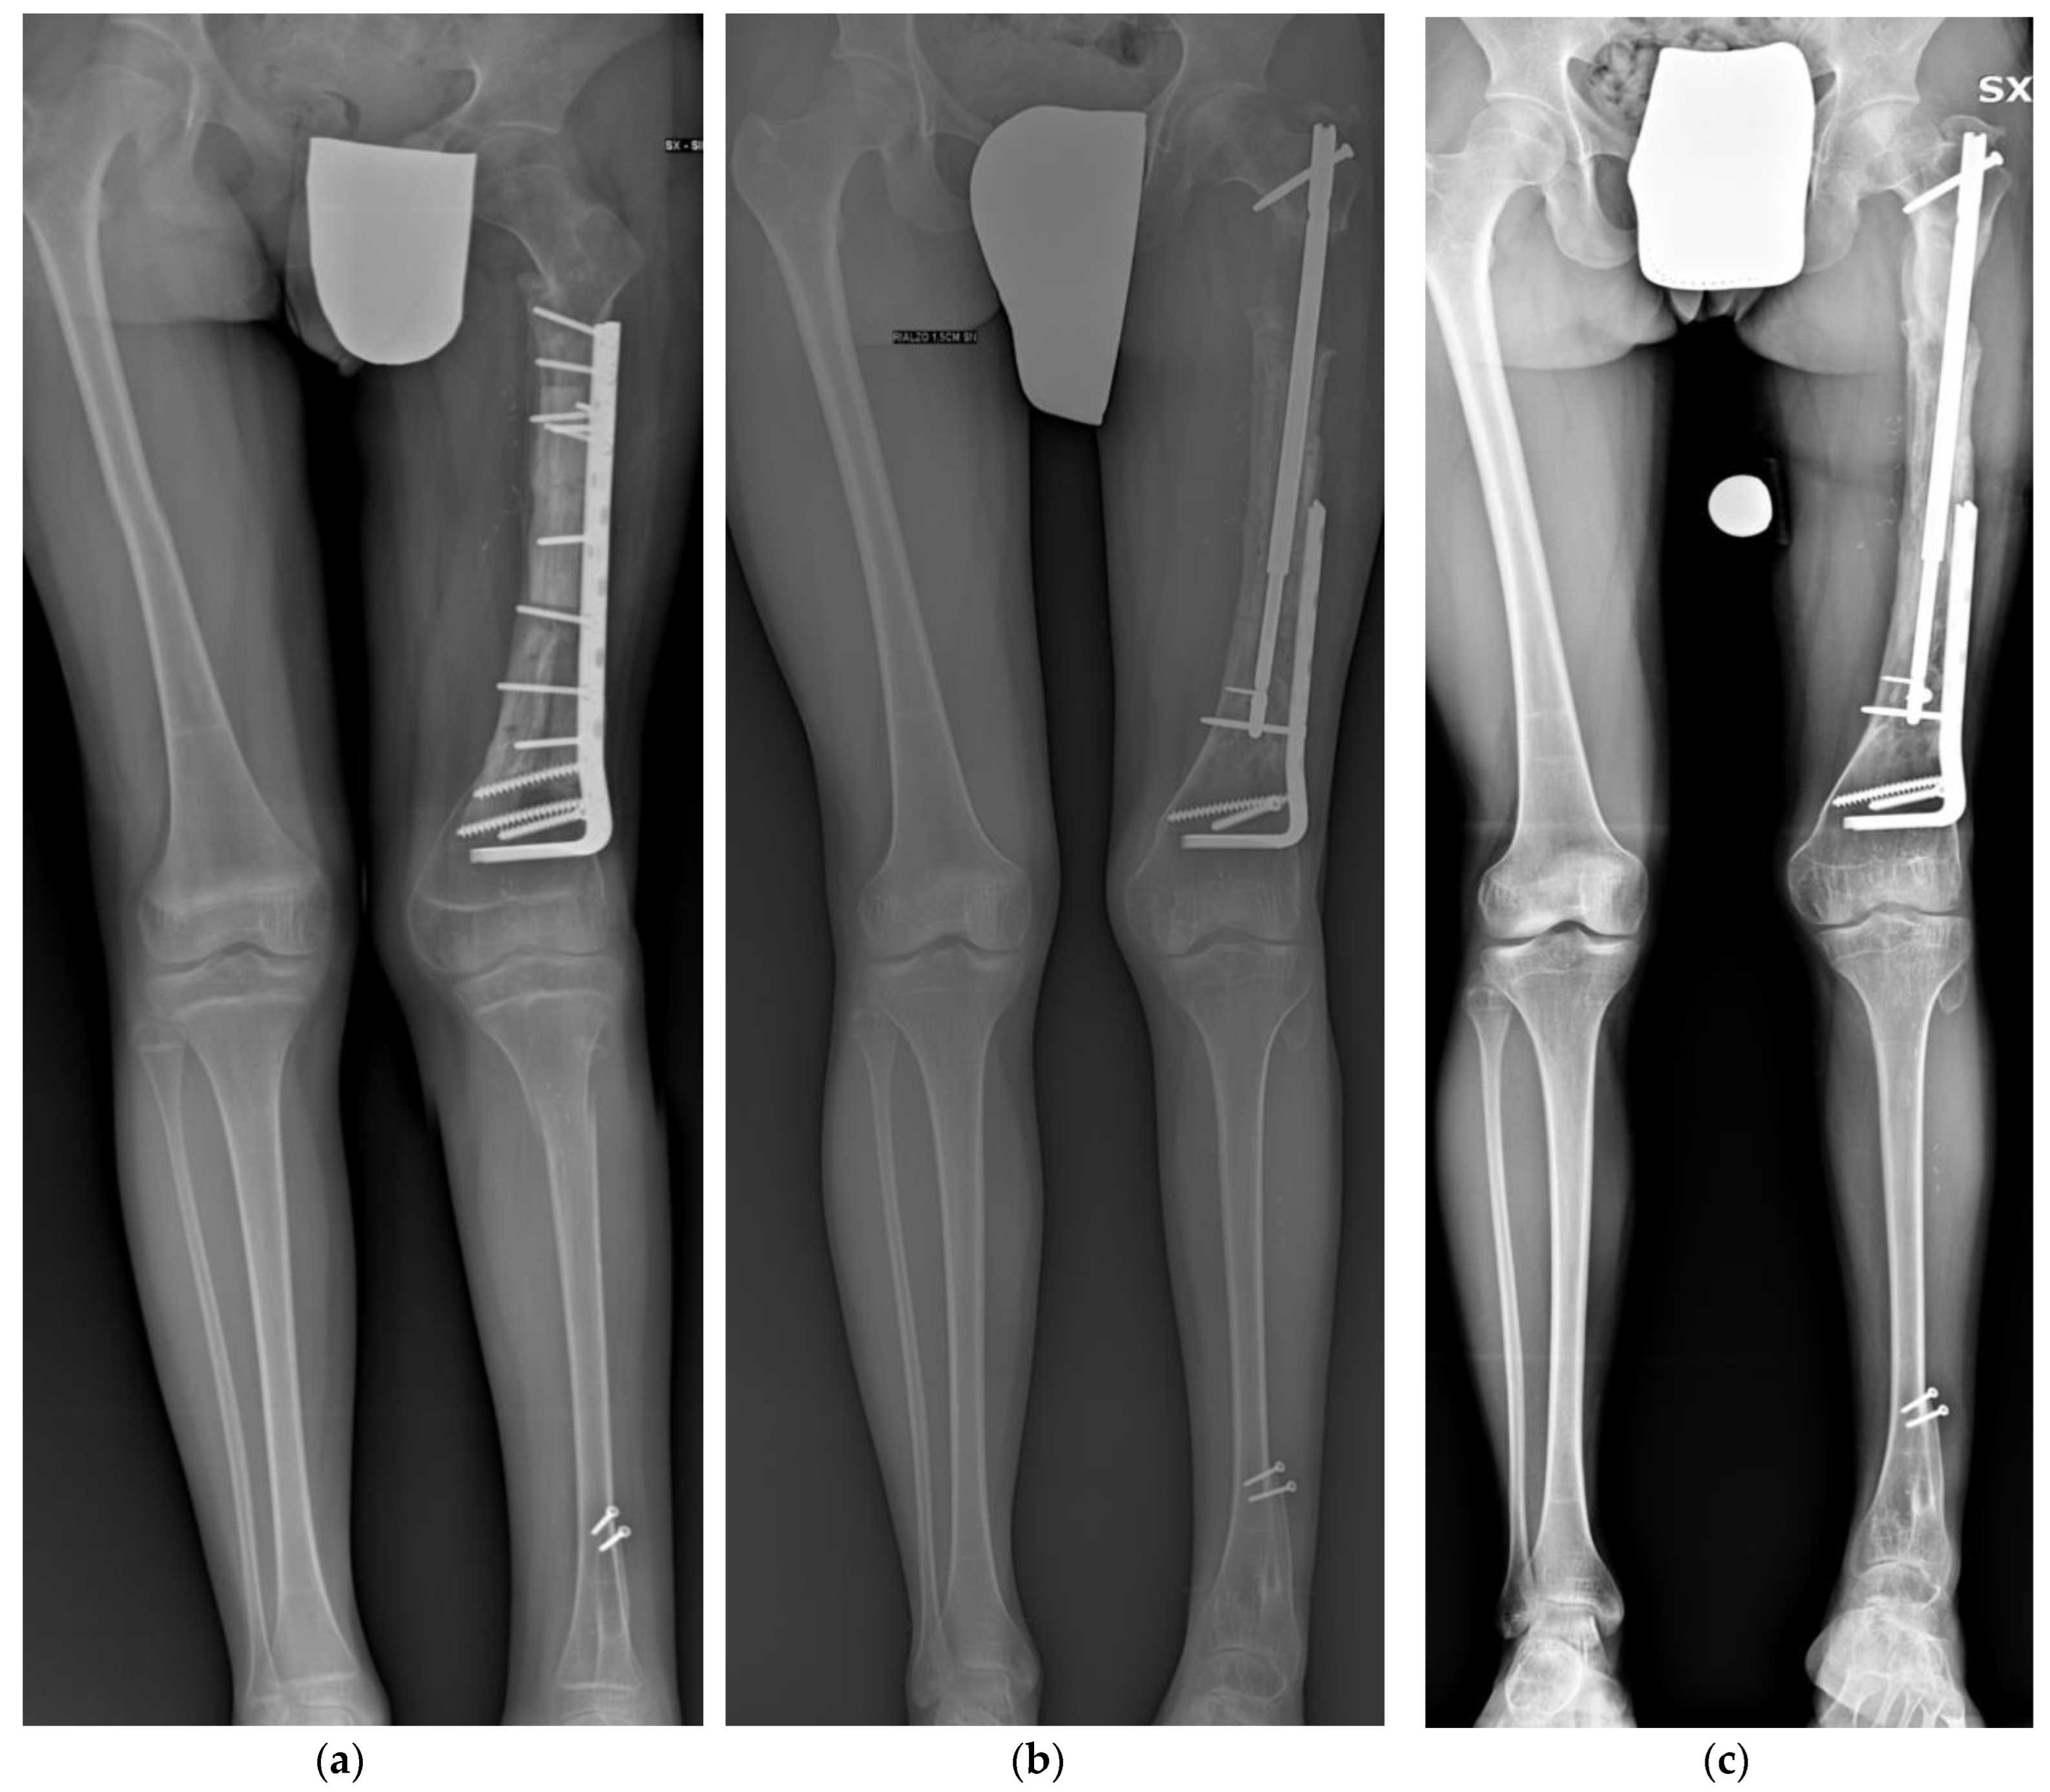

Figure 1.

(a) Illustrative case of a 12-year-old male patient treated for distal femur osteosarcoma with femoral diaphysis resection and massive intercalary bone graft and vascularized fibula. The achieved LLD was 7 cm at the end of bone growth. (b) Antero-posterior panoramic lower limb radiography at the end of the lengthening. (c) Antero-posterior panoramic lower limb radiography showing complete healing 3 months after the lengthening. Patient presented a residual LLD of 2 cm and valgus.